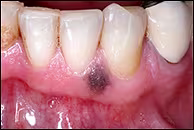

A Pigmented Lesion of the Mandibular Facial Gingiva

A 55-year-old white male was referred by his dermatologist for evaluation of an asymptomatic dark brown lesion on the mandibular facial attached gingiva.